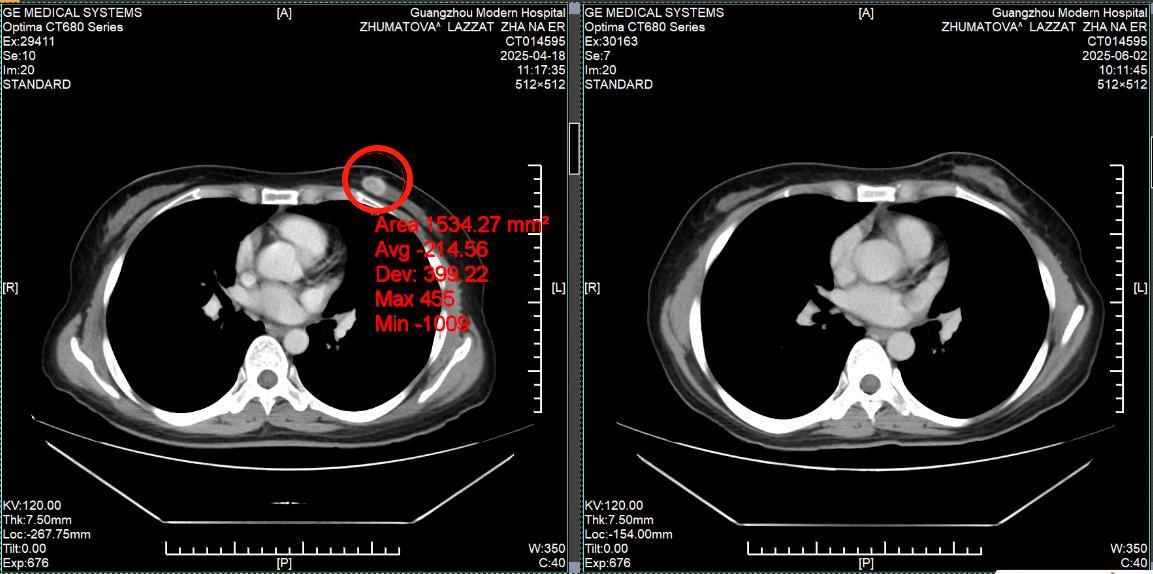

КТ-снимки подтвердили: динамика положительная, болезнь отступает

26 февраля 2024 года результаты КТ показали, что опухоль легкого значительно уменьшилась